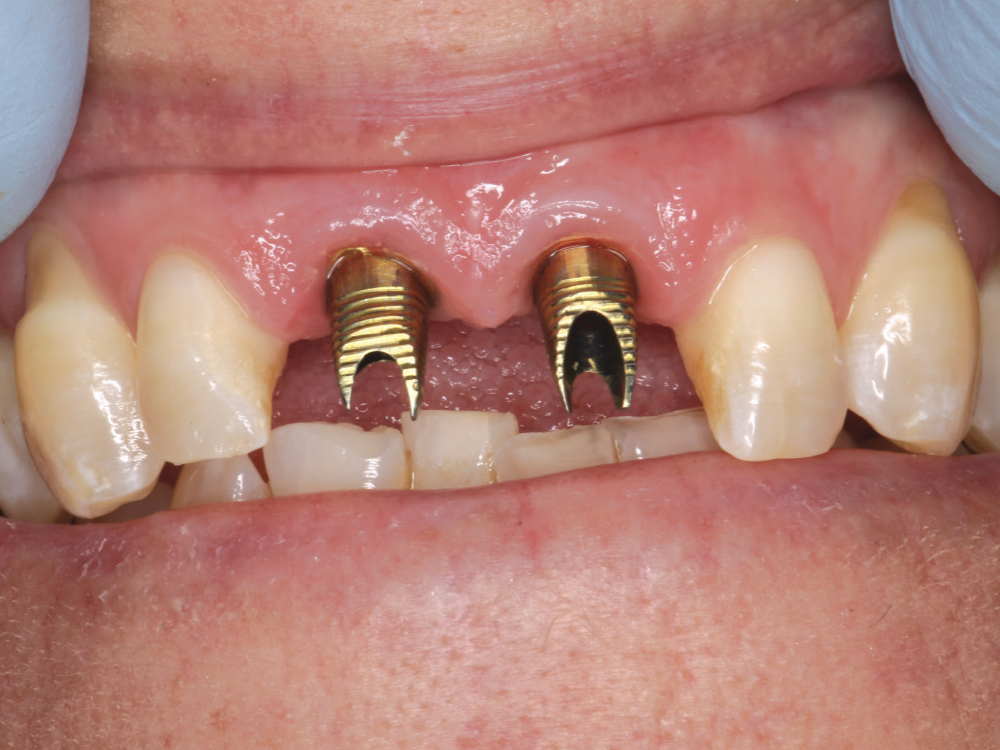

Endodontically treated tooth

Teeth needing extraction

After taking care to atraumatically remove the central incisors while avoiding damage to the buccal plate, two 3.5-mm-diameter Hahn Tapered Implants were placed into the extraction sockets. The pronounced thread design of the implants helped maintain proper position against the palatal wall during placement. The gaps between the implants and the extraction sockets were filled with Newport Biologics™ Mineralized Cortico/Cancellous Allograft Blend (Glidewell Direct).

The Hahn implants achieved high primary stability, allowing for immediate provisionalization. Temporary screw-retained crowns were fabricated chairside and connected to the implants, providing the patient with fixed “teeth in a day” that would help facilitate an esthetic outcome by sculpting the gingival tissue during healing.

Gold-tone custom abutments

Scanner view of abutments